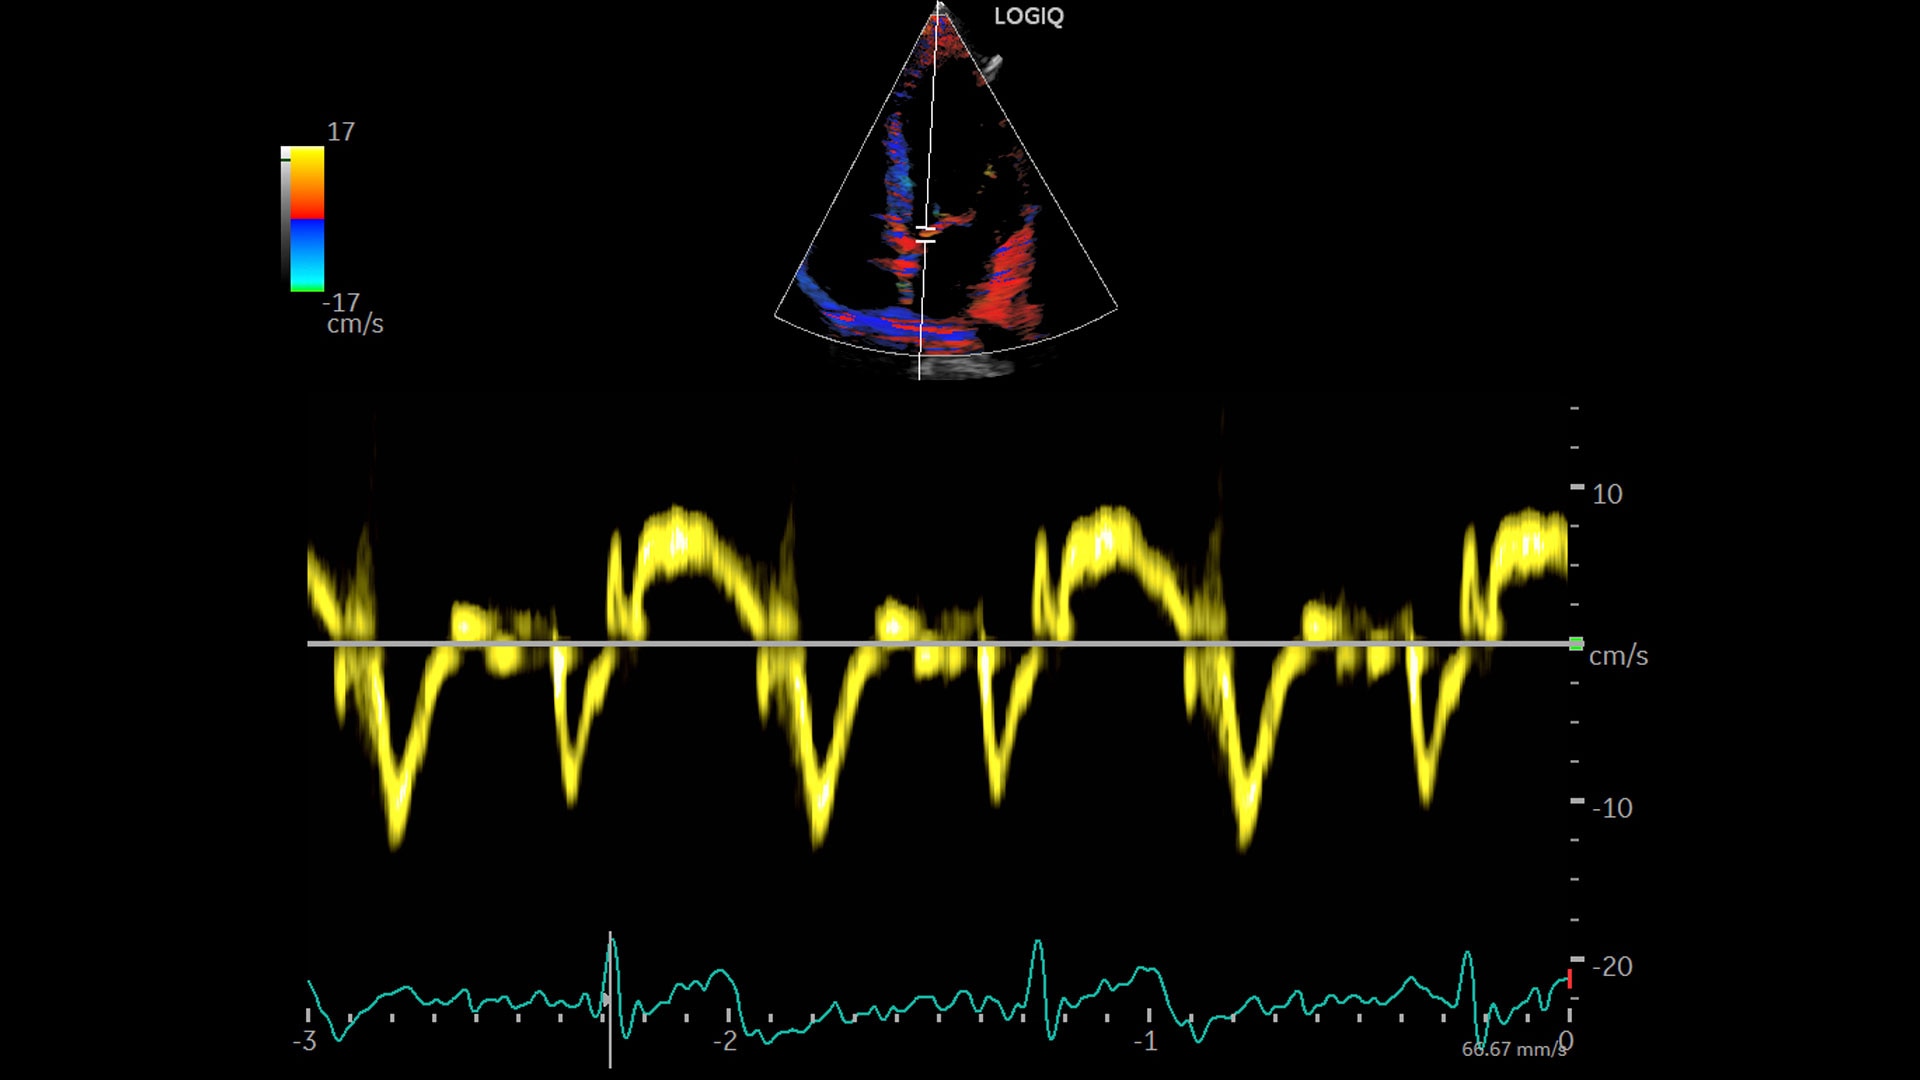

LOGIQ™ P Series

Personalized workflow tools and automation, for efficiency. Expanded patient-centric diagnostic capabilities, for flexibility. And powerful support, for long term value.

LOGIQ P Series ultrasound brings you advanced ways to increase everyday efficiency—tools and functions you can customize to your own preferences so exams flow easily, your way. Plus access to industry-leading cybersecurity, data management, and educational resources to help you optimize system uptime and utilization, while enhancing user skills.

Expanded patient-centric diagnostic capabilities for flexibility

Manage simple to complex cases with the LOGIQ P Series.

Multi-purpose capabilities, including liver, cardiac, OB/GYN, vascular, breast, thyroid, musculoskeletal, urologic, and pediatric studies.

Superb image quality with XDclear probes: Powerful high fidelity and broad bandwidth produce high resolution images whether scanning superficial or deep targets.

Advanced imaging and visualization tools, including:

• 2D Shear Wave Elastography

• Ultrasound-Guided Attenuation Parameter (UGAP)

• CEUS

• B-Flow and B-Flow Color

• 3D/4D with SonoRenderlive

• Stress Echo